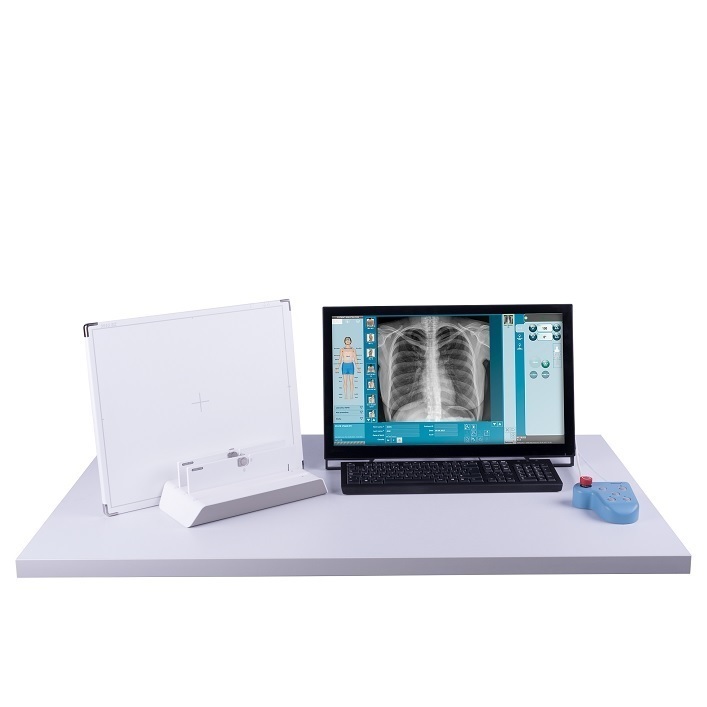

The ddRAura™ DRive Kit converts existing analog or CR radiography systems into fully integrated or interfaced digital radiography rooms, extending the life of the existing equipment while increasing productivity and reimbursement. The ddRAura™ DRive kit is available with multiple flat panel detector configurations both fixed and wireless, providing excellent image quality in a fraction of the the time as compared with Analog or CR based Radiography.

The lightweight and rugged 10” ddRAura™ Drive Kit mobile tablet based workstation can be used with any analog room or mobile x-ray system utilizing the auto – detection functionality of the flat panel detector to acquire images from any x-ray source. The tablet can also be docked and connected to a full screen monitor.